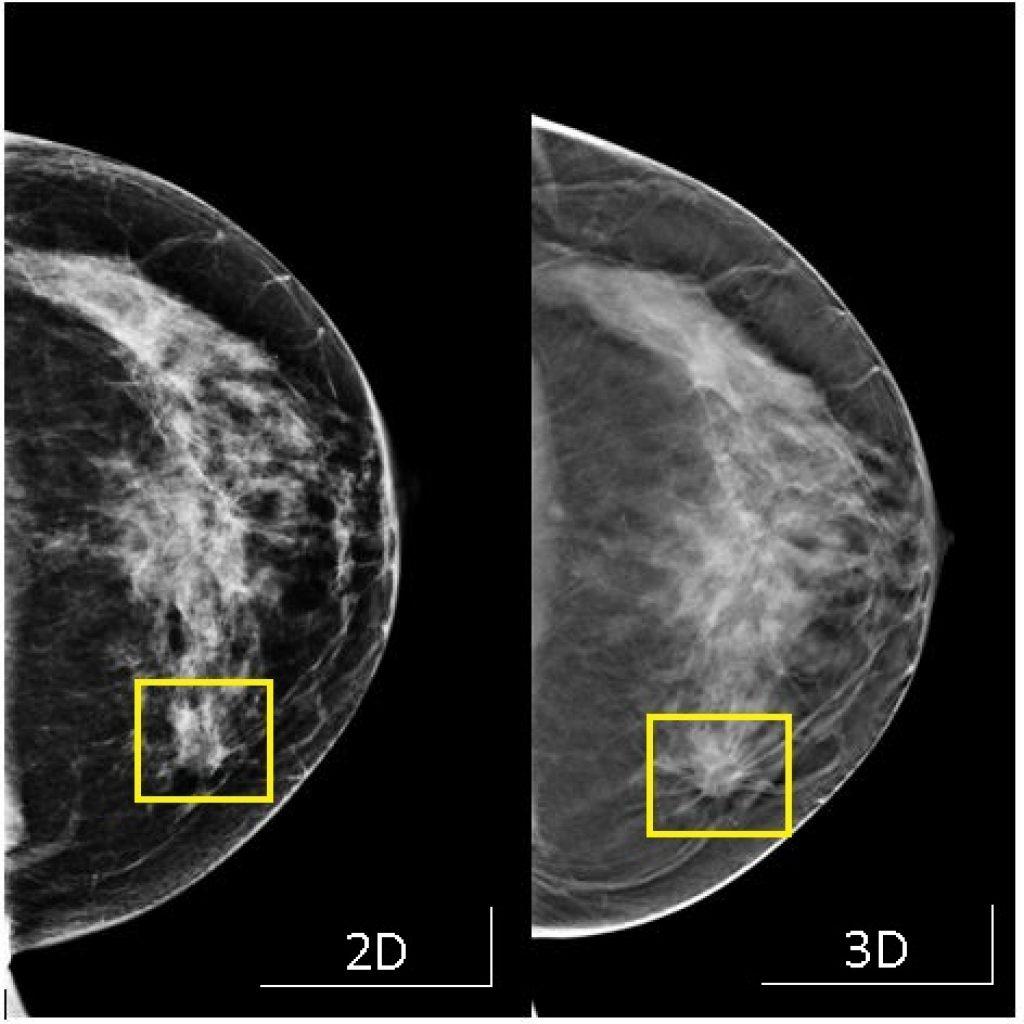

乳癌是最常見的女性癌症,本港每14名女士便有一人最終會患上乳癌。乳房造影檢查是及早發現乳癌的有效方法,美國一項有逾百萬女性參與的大型研究發現,3D立體乳房造影檢測乳癌的準確率比傳統2D造影高逾兩成,尤其有助偵測乳房組織密度較高女士的異常情況。

資料顯示,沿用多年的2D乳房造影,從乳房正面和側面拍攝再組合成一個影像,以致部分區域可能會出現重疊,而檢測乳房的準確率約為87%。至於3D乳房造成則從不同角度拍攝影像,呈現每一層乳房組織的狀態,再利用電腦製成立影像。